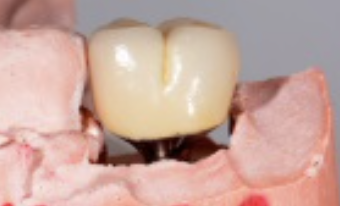

Following the recommendations of Yi, the transmucosal portion of the prosthetic connections should be flat or concave in profile diverging no more that 30 degrees from the long axis of the implants.19 Standard abutment profiles which are flat or convex in profiles are good examples to follow (Figure 19). Following Yi's recommendations individual posterior custom abutments with narrow implants should have flat or concave transmucosal profiles like a standard implant abutment with convex intaglio shapes like pontics that are cleanable with dental floss19 (Figure 20 through Figure 28).

(26.) Premolar custom abutment.

Figure 26

(27.) Premolar custom abutment.

Figure 27